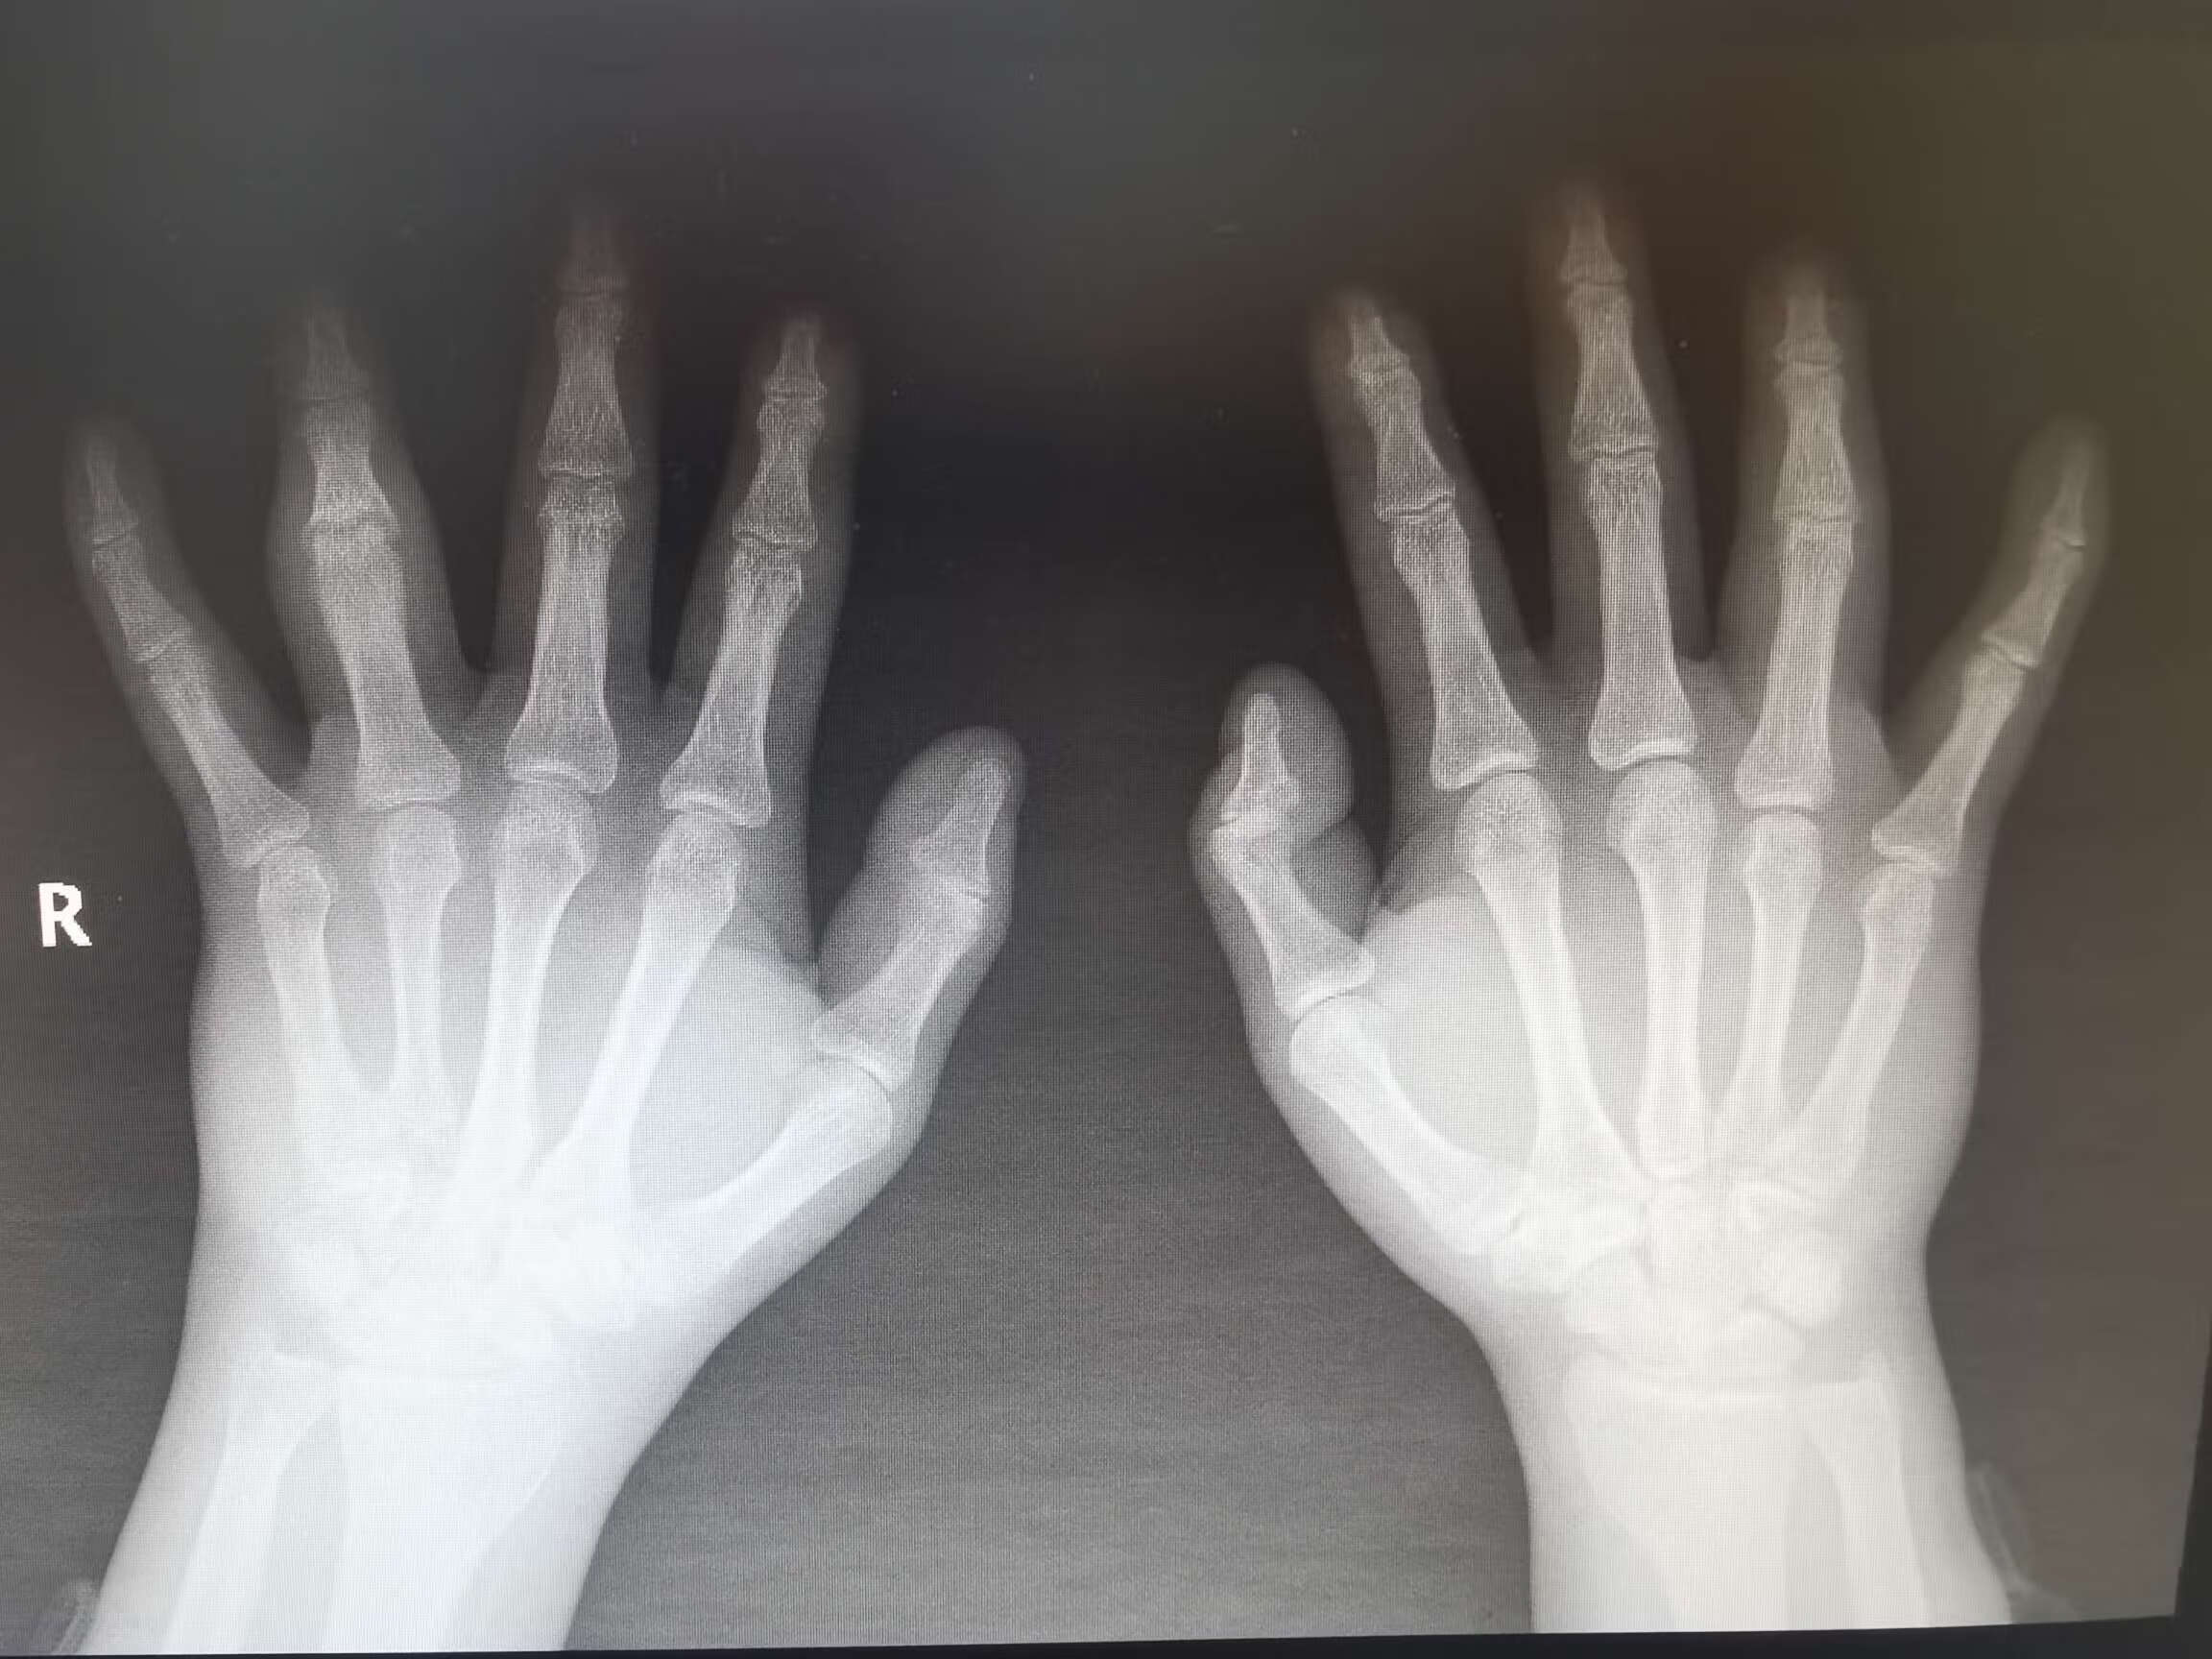

影像学检查:X光、超声、磁共振成像(MRI)等影像学检查,有助于观察关节的病变情况。如X光可显示关节间隙狭窄、骨质破坏;超声能发现关节滑膜增厚、积液;MRI则对早期关节病变的检测更为敏感,可发现软骨、骨髓的病变 。